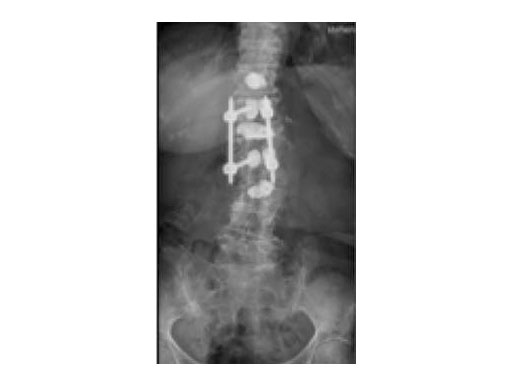

A 78-year-old woman was affected by steroid induced osteoporosis. She had persisting pain (mechanic and muscular) due to static imbalance (hyperkyphosis) and nonunion 8 months after a minor trauma with a vertebral compression fracture and vertebra plana of L1, and development of symptomatic stenosis of the spinal canal with loss of mobility over time. Pre-existing degenerative lumbar scoliosis was increased by the fracture.

A 76-year-old man was affected by advanced osteoporosis (SD -2.5) (alcohol, steroids).